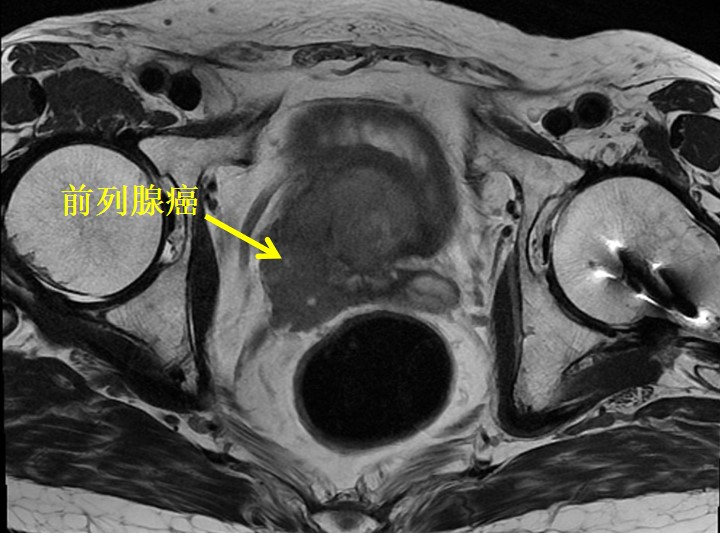

患者为60岁男性,体检时发现PSA升高,指标>100ng/ml。一周后,慕名从浙江至我院浦金贤教授专家门诊就诊。磁共振提示:前列腺中央带腺体及外周带前列腺癌,建议穿刺活检,盆腔左侧淋巴结增大。我院穿刺病理提示:前列腺腺癌,Gleason分级评分4+4=8分,双侧受累。患者PSA升高明显,磁共振下显示盆腔淋巴结肿大,考虑肿瘤负荷较高,预后不佳。浦金贤教授决定行腹腔镜下根治性前列腺切除+盆腔淋巴结清扫术,力求彻底切除肿瘤,提高远期生存。